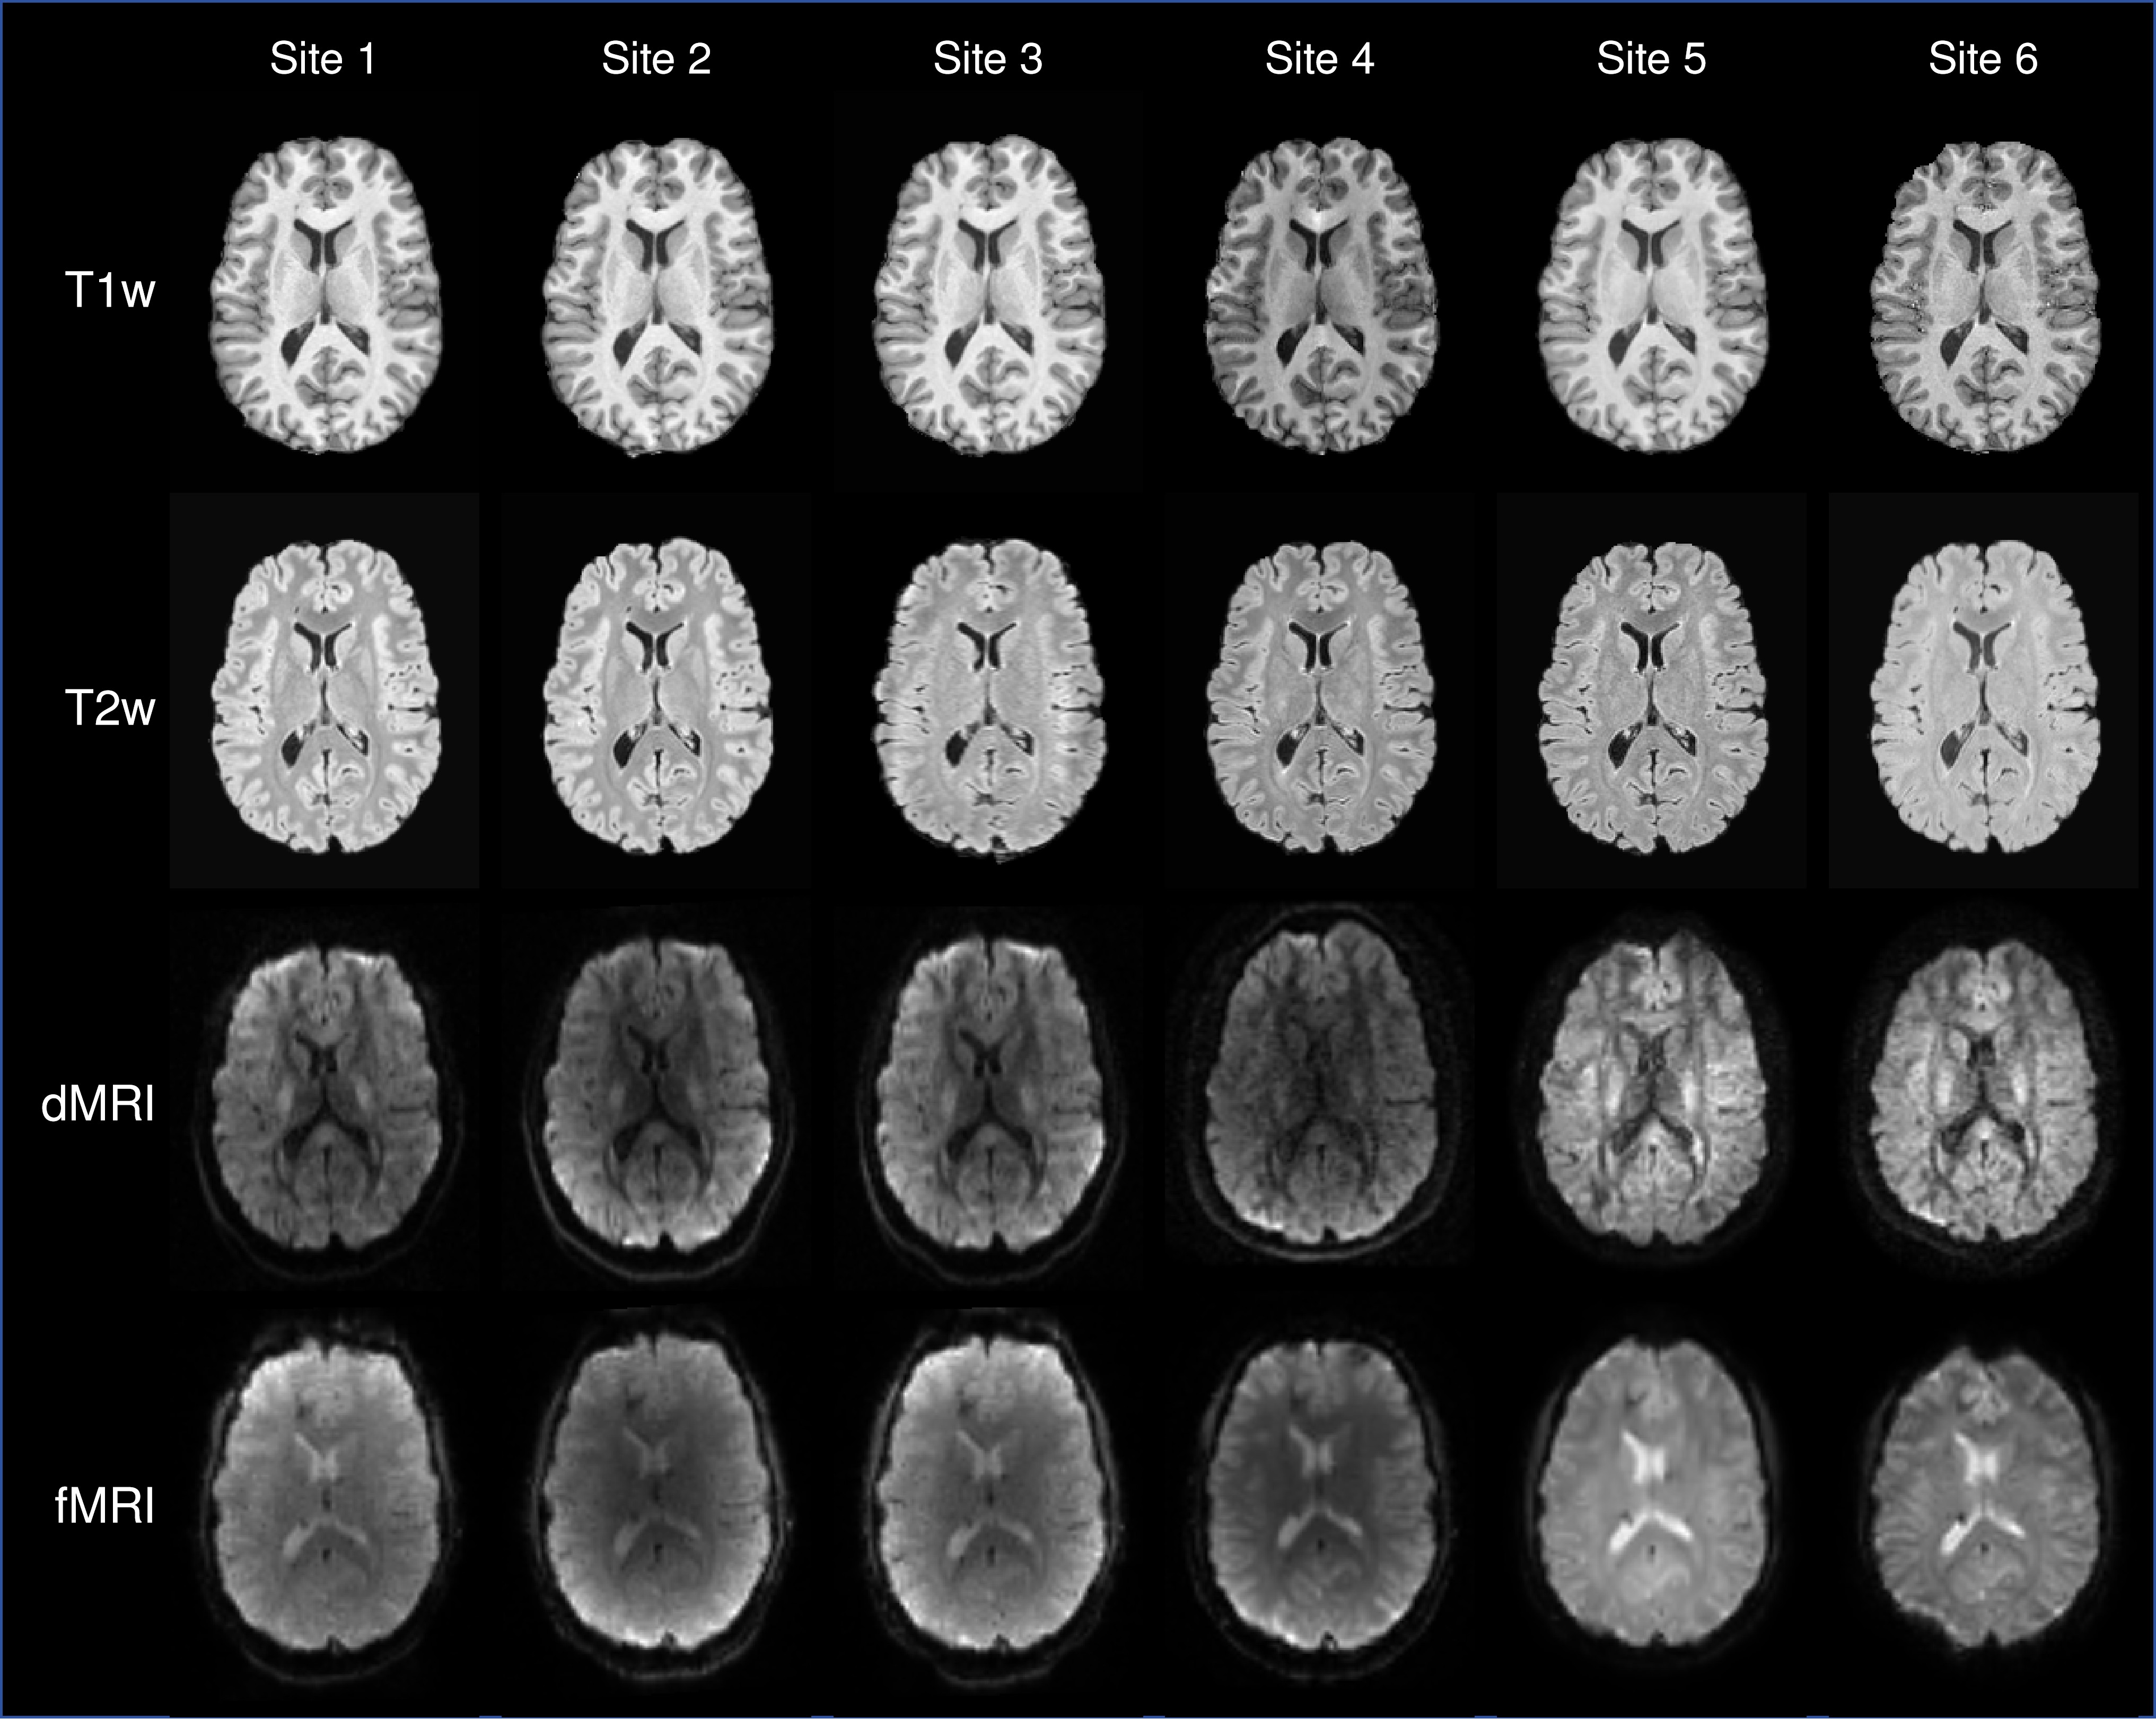

Taking ON-Harmony [130] as an example, 20 healthy volunteers were scanned using five imaging modalities across six scanners from different vendors and models. These modalities included structural imaging (T1-weighted, T2-weighted, and susceptibility-weighted imaging) as well as functional imaging (dMRI and resting-state fMRI). As shown in Figure 6, a clear observation is that functional modalities exhibit substantially greater inter-scanner variability than structural ones. This discrepancy arises not only from differences in reconstruction and post-processing pipelines across scanners, but also from the fact that both dMRI and fMRI typically rely on fast echo-planar imaging sequences for data acquisition, which are more susceptible to imperfections such as field inhomogeneities.

Refer to caption

Figure 6: Representative examples of different modalities for a single participant data across all scanners from ON-Harmony dataset [130].